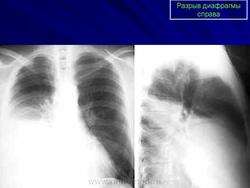

ОГК. Травмы диафрагмы. +

Разрыв диафрагмы.